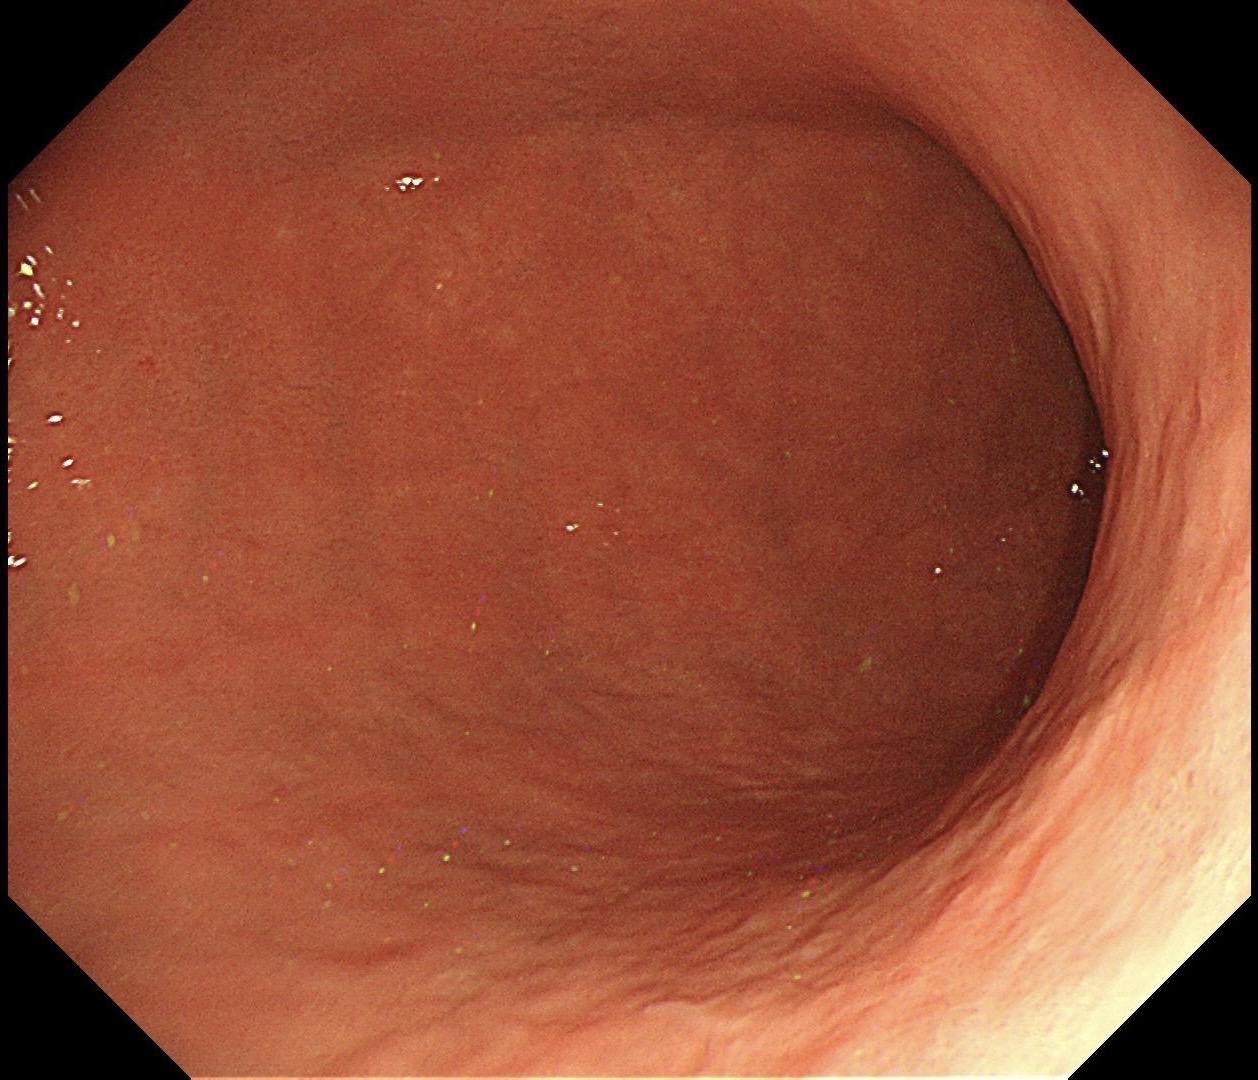

男,40岁,胃双发褪色调病变。慢性胃炎复查,3年前胃镜未见异常,Hp阳性背景,萎缩不明显,胃体下部大弯见一褪色调病变,浅凹陷,5mm左右,换用放大内镜观察,表面结构缺失,血管异型明显,未分化可能性大……胃窦后壁见一白斑,无高度差,NBI浅茶色,放大草草看了下,似有边界,IP增宽,活检待病理……小哥哥胖得几乎没脖子,腹式呼吸太明显~😖